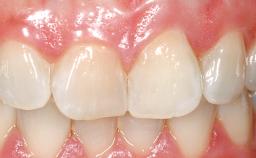

Immediate Placement of an Implant in a Maxillary Right Central Incisor Site

A 30-year-old female patient was referred to the office for the treatment of tooth 11. Her chief concern at the initial visit was to inquire, “Why is my tooth pink?” Upon clinical examination, it was determined that tooth 11 had a previous history of trauma and that the clinical crown had become noticeably pink in color as a result of internal resorption. This diagnosis was confirmed radiographically, indicating a large radiolucency involving the central and distal portions of the clinical crown. It was determined that restoration of this tooth was not possible, and that extraction was indicated. The presence of a mid-line diastema, which the patient wanted to reproduce, directed the treatment plan for tooth replacement utilizing a dental implant.

Prosthesis Type FDP

SAC Level Advanced

Esthetic Risk High